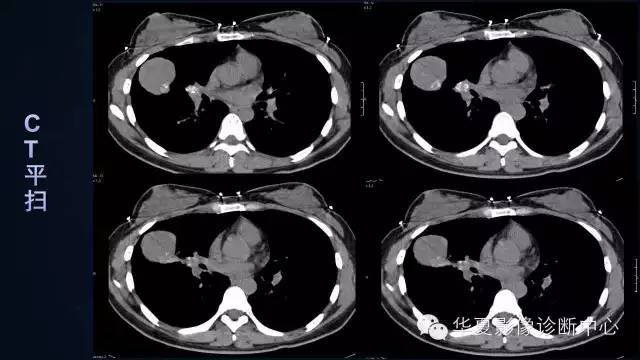

【病例】肺肉瘤样癌1例CT影像表现